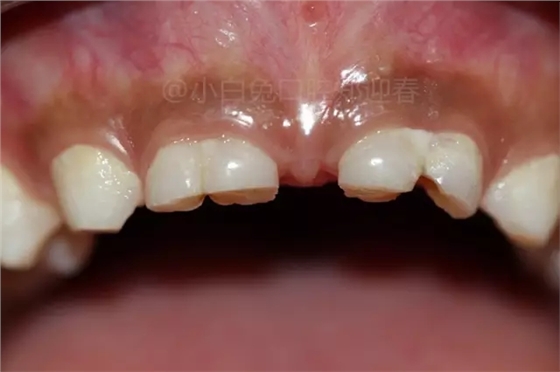

患兒,10歲,因上前牙未替換來(lái)診,查體:輕度反合,51和52、61和62均融合,且存在間隙約4mm,全面曲面斷層片顯示:11、21未萌,52、51、61、62牙根均有不同程度的生理性吸收。